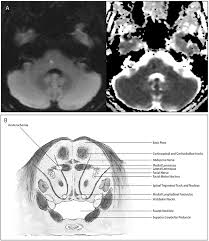

Structures Affected In Lateral Pontine Syndrome A Transverse View Of Download Scientific Diagram